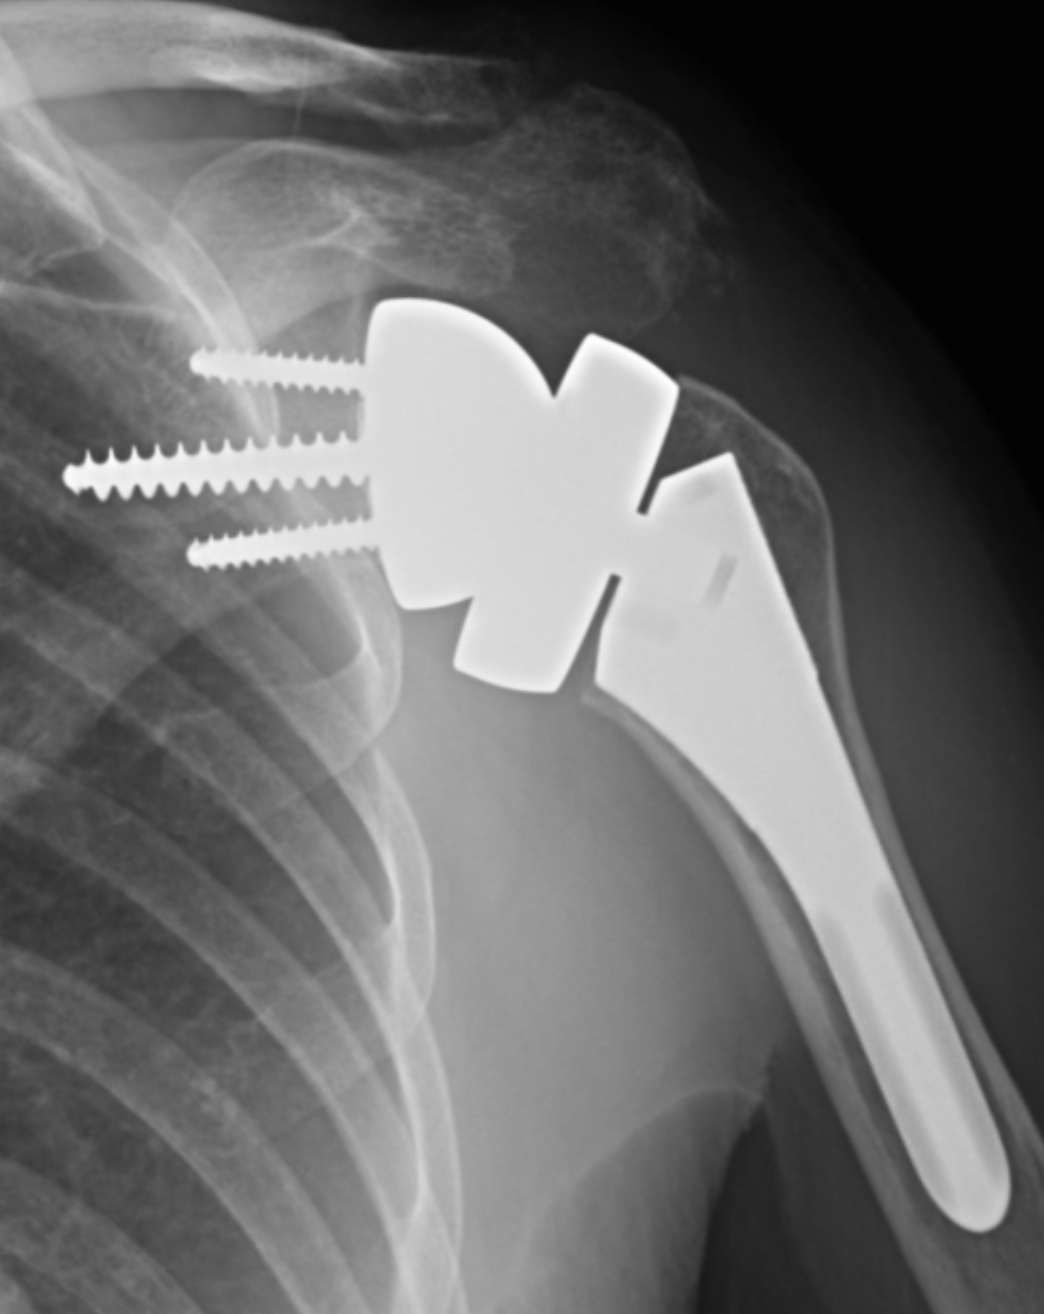

3. Reverse Shoulder Replacement:

What to Expect with a Reverse Shoulder Replacement? Click hereDesigned for cases with rotator cuff deficiency or significant bone loss. The positions of the ball and socket are reversed to allow other muscles (like the deltoid) to compensate for the damaged rotator cuff.

When the rotator cuff is torn, it weakens the shoulder joint and can lead to shoulder arthritis over time. This specific type of arthritis caused by a long-standing rotator cuff tear is called rotator cuff arthropathy.

The reverse shoulder replacement ‘flips’ the design:

- The metal ball is placed on the shoulder blade (glenoid)

- The plastic socket is placed on the top of the arm bone (humerus)

- This reversed configuration allows the deltoid muscle, the large muscle on the outer shoulder, to take over much of the function normally performed by the rotator cuff, improving both movement and joint stability.

Comprehensive® Reverse Shoulder System Augmented Baseplate ~ Zimmer Biomet